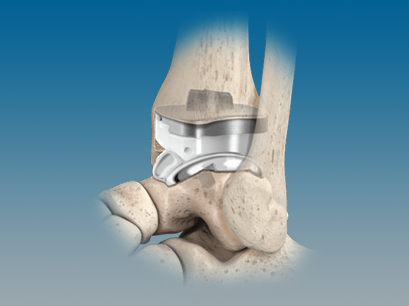

QUANTUM® Total Ankle System with OrthoPlanify™ Patient Specific Instrumentation